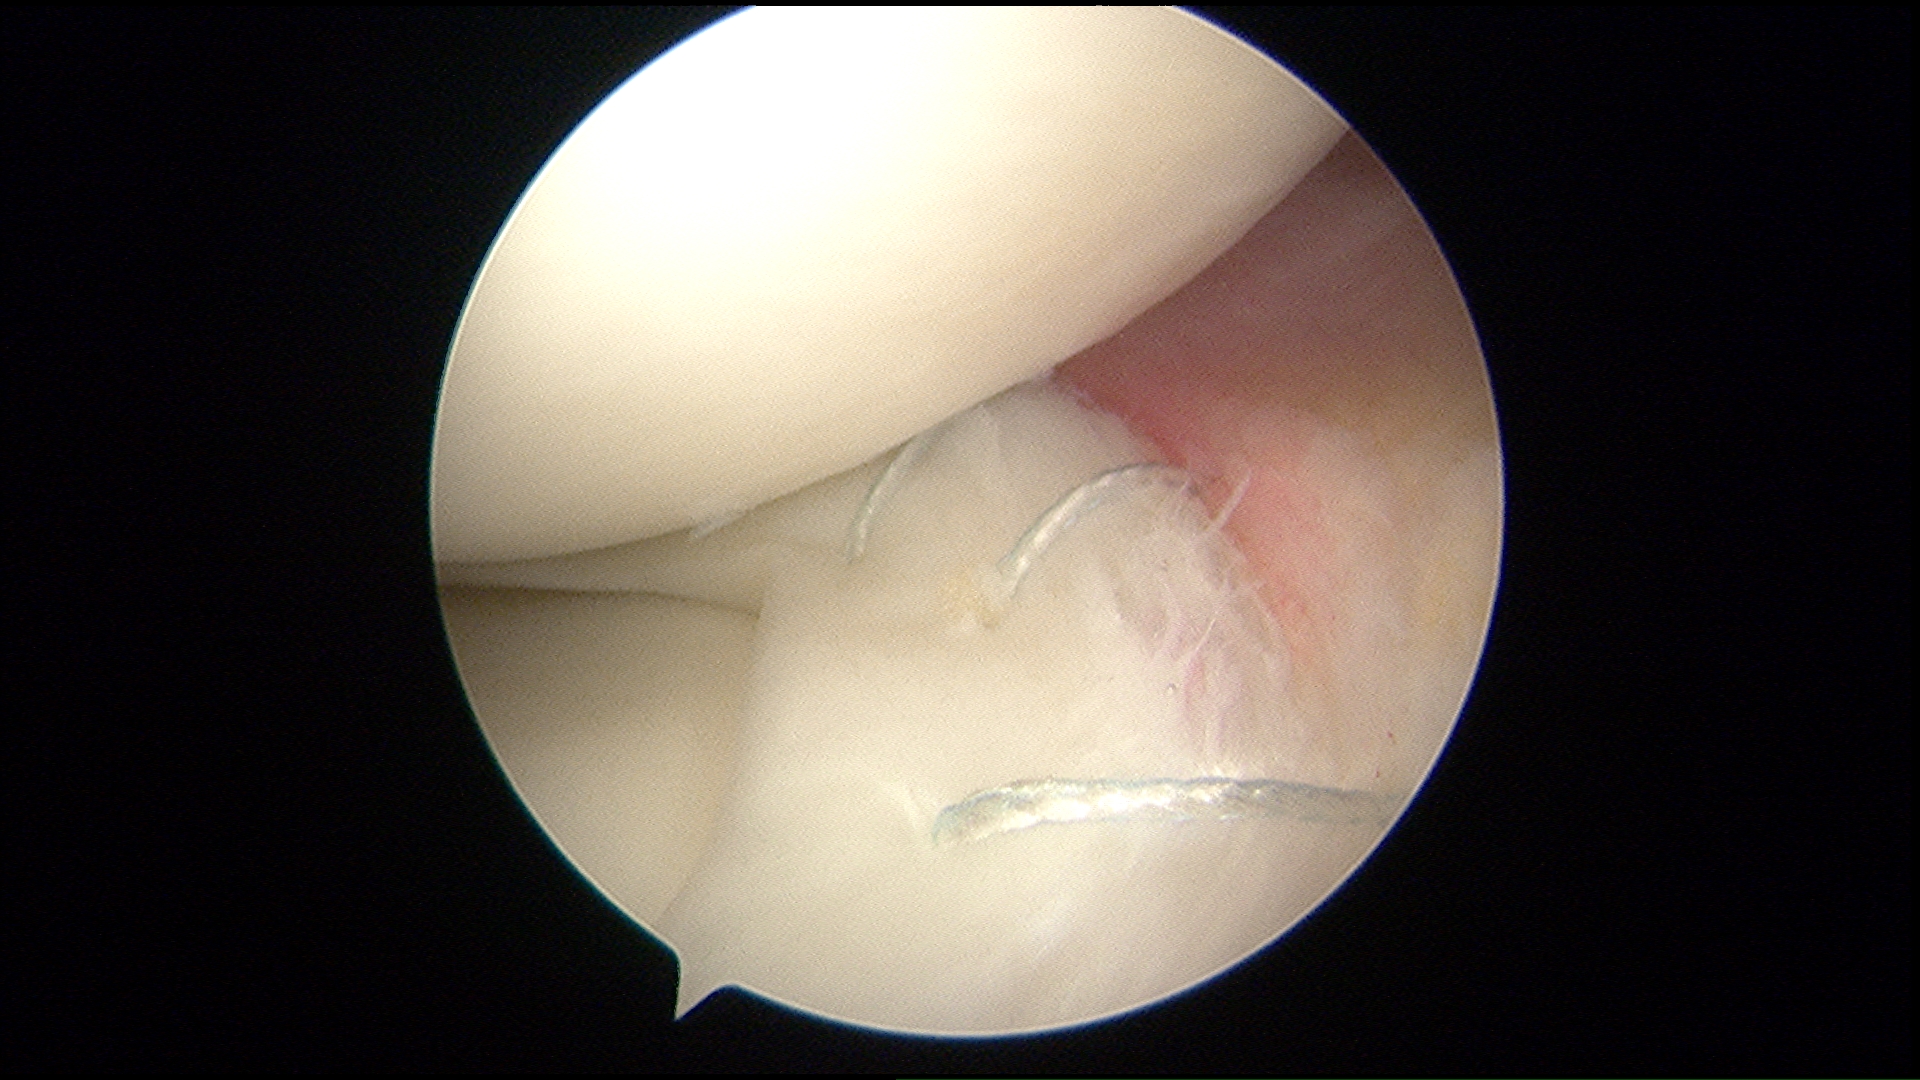

- Knee arthroscopy: One of the most commonly performed surgical procedures, includes inserting a miniature camera into the knee through a small incision. This provides a clear view of the inside of the knee, which Dr. Ahmad uses to insert surgical instruments through to trim or repair your tear.

- Partial meniscectomy. In this procedure, the damaged meniscus tissue is trimmed away.

- Meniscus repair: Some meniscus tears can be repaired by suturing (stitching) the torn pieces together. Whether a tear can be successfully treated with repair depends upon the type of tear, as well as the overall condition of the injured meniscus. Because the meniscus must heal back together, recovery time for a repair is much longer than from a meniscectomy.